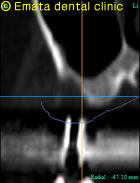

患者さんは、右上奥歯をインプラント治療を希望されて来院された62才の男性の方です。上顎洞底の位置が低く、CT撮影で外側の骨も喪失してることがわかりました。奥歯の上には上顎洞という空洞(黄色の矢印の線)がありこのままではインプラントが上顎洞内に突き抜けてしまうためインプラントの手術ができません。

CT画像

インプラントが2本はいりました。上顎洞(黄色い線)があがったのがわかりますね。